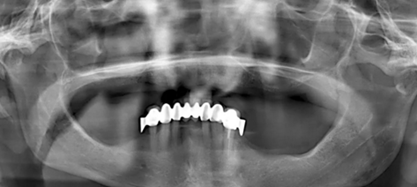

為了最大程度利用現(xiàn)有骨量,需要一個全程引導(dǎo)式的種植外科手術(shù)導(dǎo)板。在“以修復(fù)為導(dǎo)向”的方案設(shè)計過程中,根據(jù)CBCT數(shù)據(jù),對種植體與基臺中心軸向之間可能的最大夾角進(jìn)行計算。同時,計劃拔除 21 牙位之前未發(fā)現(xiàn)的殘根。該牙根之所以至今才檢測到,是因?yàn)榍鏀鄬悠?(OPG) 上呈現(xiàn)出影像重疊(圖 1)。

(圖1)